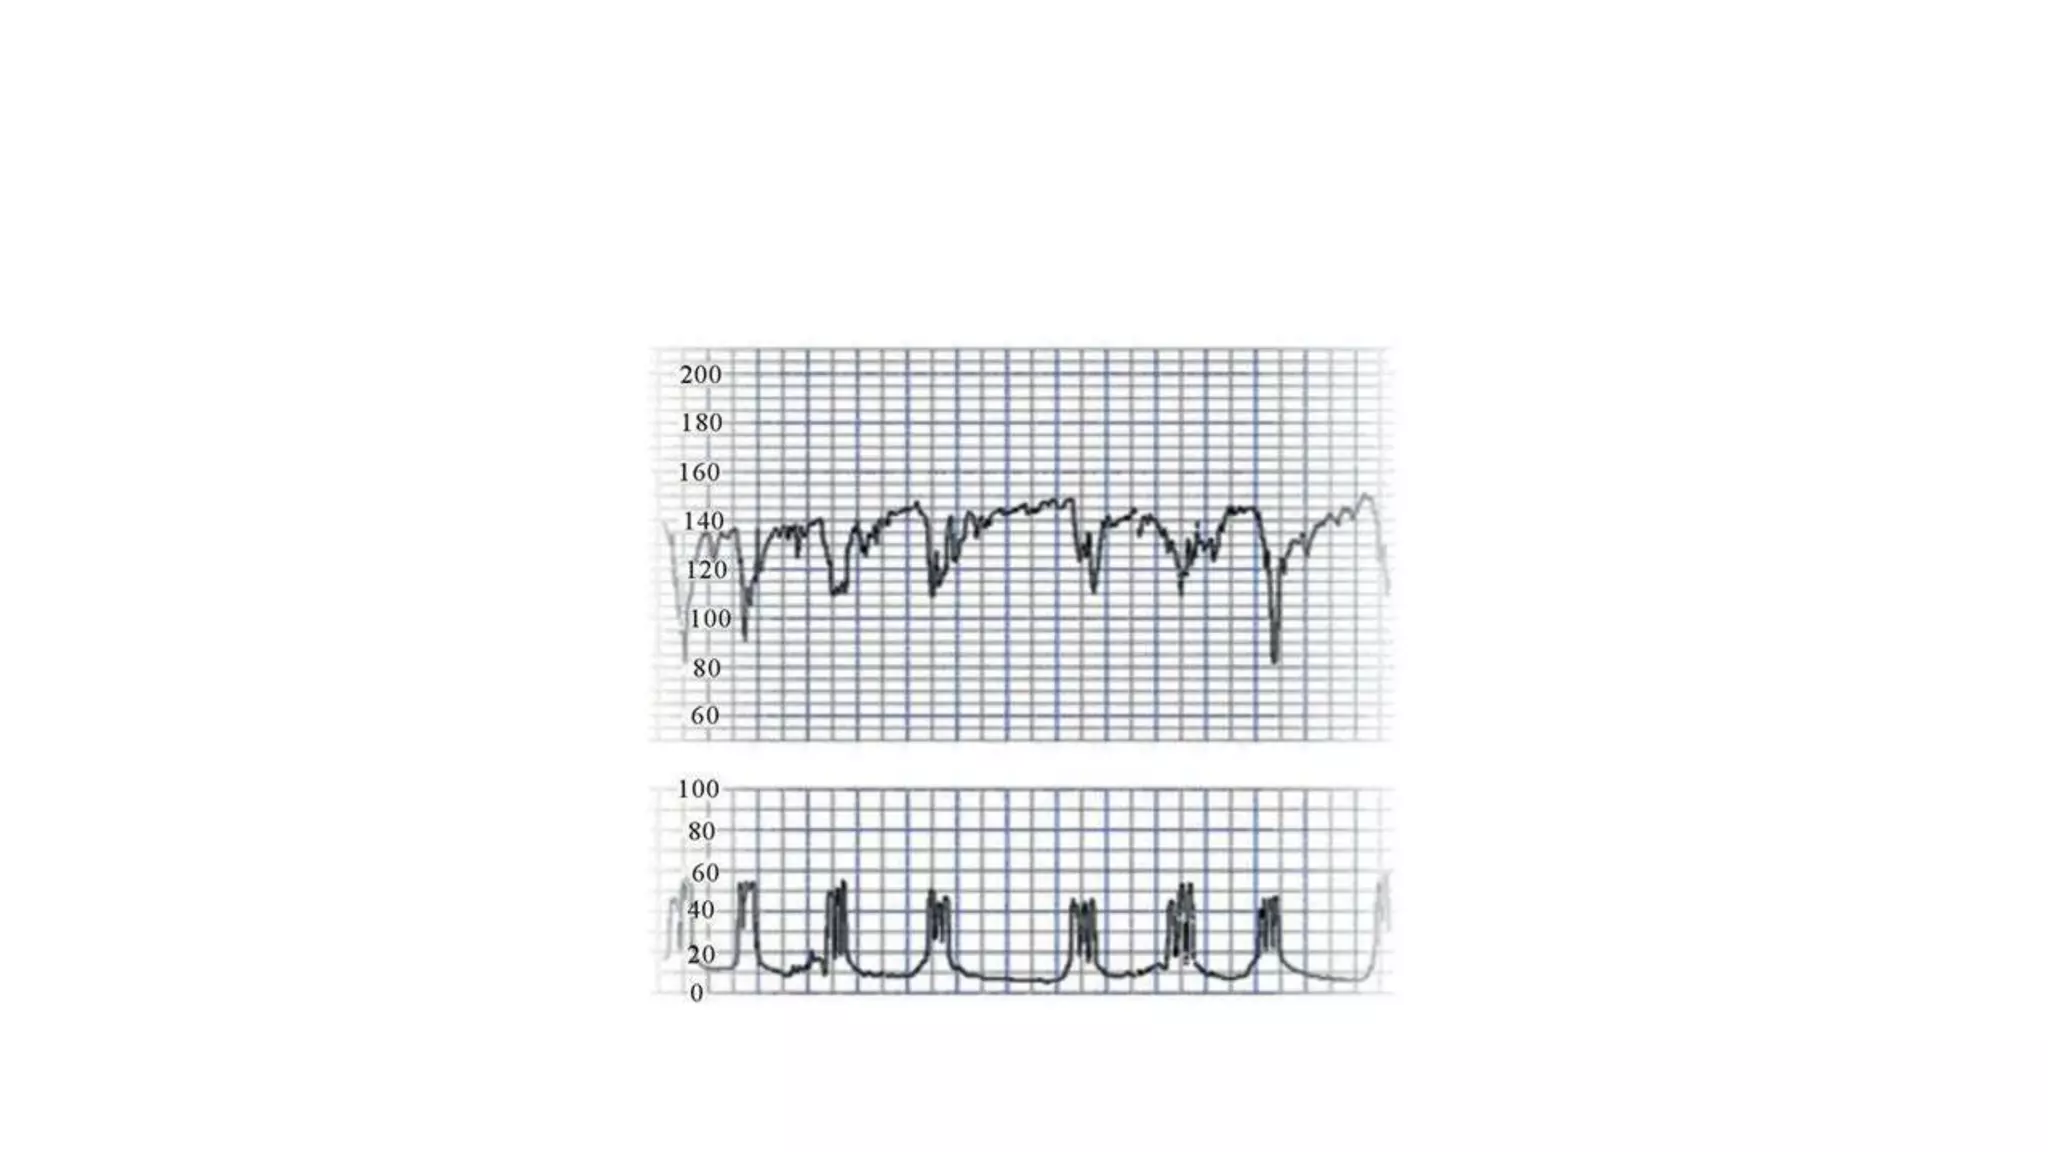

The document discusses key metrics for monitoring a baby's heart rate in utero, including the normal baseline rate of 100-160 bpm and variability. It also covers types of accelerations and decelerations that can occur, such as early or late, as well as bradycardia, which is an abnormally slow heart rate.